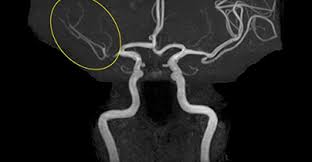

- MRA (자기공명혈관조영술): MRI 원리를 적용해 **혈관 내부 구조와 혈류 흐름**을 3D 영상으로 확인하는 검사입니다. 동맥류, 혈관 협착·폐쇄·혈전 등의 진단에 사용됩니다 :contentReference[oaicite:2]{index=2}.

- MRA 장점: 혈관 질환(협착, 동맥류 등) 진단에 특화, **비침습적이고 방사선 노출 없음** :contentReference[oaicite:9]{index=9}.